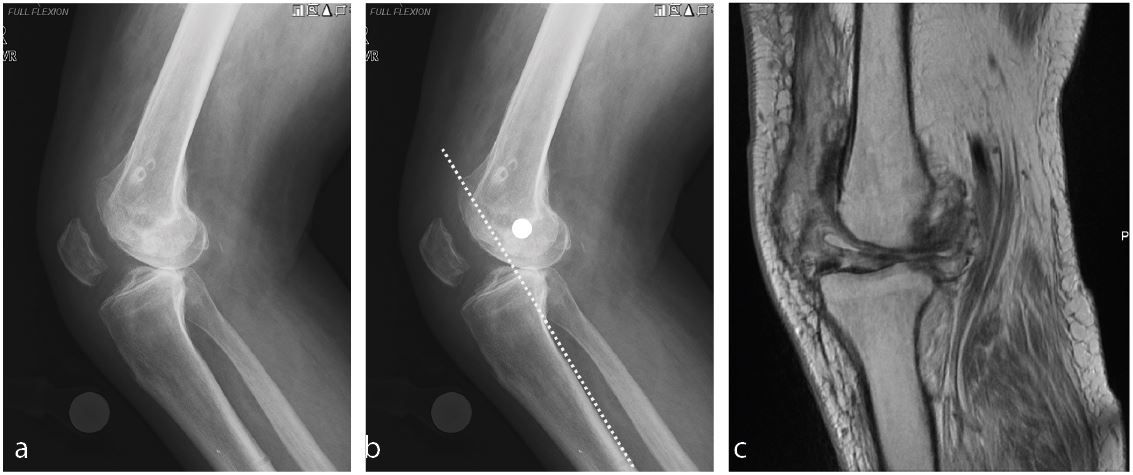

Osteoarthritis in patients with a subluxated or dislocated knee

The stiff and subluxated knee can be a very challenging problems to deal with. First one needs to have a level of suspicion when encountering severe flexion contractures after ligament injuries or knee dislocation. While some posterior subluxation of the femur on the tibia is the hallmark of progressive osteoarthritis in the anterior cruciate ligament (ACL) deficient knee it is important to identify patients with more advanced subluxation/dislocation (Figure 4a) of the femur. In my experience a warning sign is when the insertion of the MCL in the center of the femoral condyle moves beyond a line on the posterior cortical bone of the tibia (Figure 4b). In the presence of stiffness I strongly encourage a preoperative vascular work up. I well remember the one patient that I accidently opened the popliteal artery when trying to mobilize a posterior subluxated femur. Luckily, I had anticipated the complication because of the proximity of the popliteal artery to the posterior condyle of the femur on preoperative MRI imaging (Figure 4c) and the standby vascular surgeon was able to close the vascular injury from anterior enjoying the perfect exposure of an open flexion space with laminar spreaders in place.

Exposure of the knee can be quite difficult especially if the stiffness is the result of bony impingement. I remember a few patients with intraarticular distal femur fractures that had healed in such a malposition that the resulting step off blocked the flexion of the knee (Figure 9a, b, c).

Dealing with this situation in a knee with less than 45 degrees of flexion requires a very careful step by step exposure. Usually I start by performing a medial capsular release to be able to externally rotate the tibia as far as possible. Once this allows flexion of the knee to 40 to 60 degrees distal resection of the femur can be attempted. Further flexion is achieved with a free hand cut of the proximal tibia to disengage the bony impingement. Despite opening up the extension gap it can be difficult to flex the knee and expose the tibia without a femoral peel and release of the MCL (Figure 10) to allow for separation of the femur from the tibia [6].